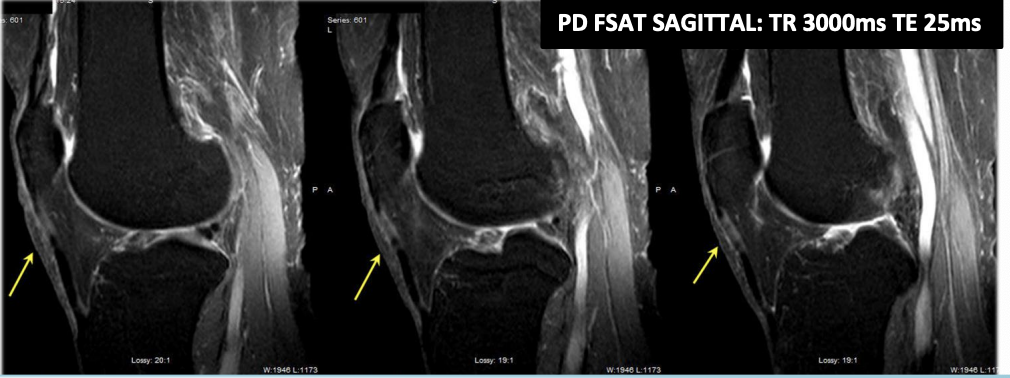

magic angle arttifact occurs when

a tendon or ligament is positioned approximately 55° to the direction of the main magnetic field, and a short TE value pulse sequence is utilized., sometimes longer flip angles

confirmation of magic angle artifact

confirmation of magic angle artifact, instead of tendinopathy, is made by the utilization of a long TE sequence, where the long T2 relaxation time of the collagen fibers will not yield high signal in the tendon at the 55° angle to the magnet.